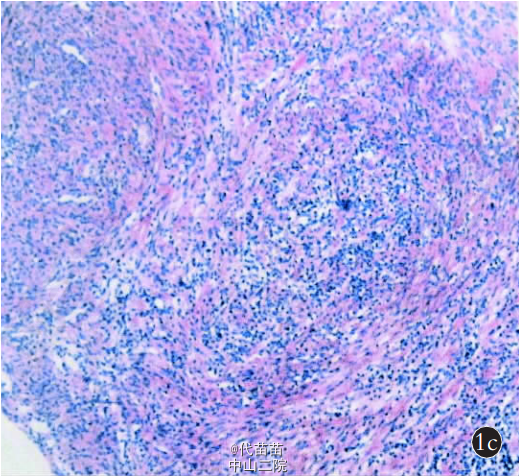

患儿,女,33 个月,因左前臂肿物 2 个 月 于 2011 年 7 月12 日来我院就诊。 患儿家属无意中发现患儿左前臂包块,花生粒大小,质硬,与周围组织分界清,无红肿及压痛。就诊于当地医院,考虑为肿大淋巴结,未予特殊治疗。 此后患儿家属自觉左前臂肿物略增大, 要求对左前臂肿物行手术切除。 查体见 :左 前 臂 上 1/ 3 背 侧 尺 骨 缘 触 及 软 组 织 肿 物 ,约 2.0 cm×1.0 cm×1.5cm 大小,位置表浅,质硬,边界清楚,活动度差,无压痛,局部皮肤无红肿,左腕关节及手指活动良好(图 1)。 彩超检查示左前臂指示部位距体表 2 mm 肌层外软组织内可见一实质性低回声光团,大小为 16 mm×6 mm×12 mm,边界清,似可见被膜,内部回声欠均匀,其内可见稀疏血流信号,提示:左前臂实质性结节,不除外肿大淋巴结。 实验室检查:尿素氮3.80 mmol/L,肌酐 57 μmol/L,尿蛋白阴性,尿酮体阴性,C-反应蛋白 1.20 mg/L,淋巴细胞百分比 0.69%,淋巴细胞绝对值4.39×109/L。 入院后完善术前检查,择期行左前臂软组织肿物切除术。 术中以左前臂外侧肿物为中心做长约 3 cm 纵形切口,切开皮肤、皮下、深筋膜层,即见肿瘤,完整剥离肿物,见肿 物包膜完整,与周围组织分界清楚、无粘连及浸润,肿物大小约 1.5 cm×1.0 cm×1.5 cm,术中注意无瘤化操作,距肿物边缘0.5~1.0 cm 处将肿物完整切除,见无肿物残留。 将肿物送检快速病理,术中快速病理示良性梭形细胞,伴炎性细胞浸润(图2)。 剩余组织送检常规病理,常规病理回报为梭形细胞丰富,伴有淋巴细胞、浆细胞等炎性细胞;病理诊断:左前臂炎症性肌纤维母细胞瘤(图 3)。 患儿家属要求行扩大切除术以防止复发,术中快速及术后常规病理报告切除组织未见肿瘤细胞。患儿术后恢复良好, 未给予免疫治疗及放化疗, 术后 1 周出院,术后随访 15 个月未见肿物复发或转移。 炎症性肌纤维母细胞瘤是一种临床上少见间叶性交界性肿瘤,由肌纤维母细胞及淋巴细胞、嗜酸性粒细胞等炎症细胞构成,性质为潜在恶性(或低度恶性)肿瘤,有复发倾向但较少发生转移。 该病的发病原因、机制尚不明确,多发生于儿童及青少年,常见于肺、肝脏、肠系膜、大网膜等部位,偶见于舌部、下颌、头颈、泌尿系统等,发生于软组织者少见。 炎症性肌纤维母细胞瘤呈缓慢性增长,通常无全身症状,实验室检查无明显异常,仅表现为局部肿块引起的相应的症状和体征,临床上无特异性表现,影像学及实验室检验诊断本病很困难, 其确诊主要依靠病理组织学诊断,分为3 种 组 织 学 类 型 :黏液型 、梭 形 细 胞 密 集 性 和 纤维型。本例患儿除左前臂可触及肿块外,无发热头痛等症状,检查及检验亦无特异改变,术前明确临床诊断较为困难,完整切除肿物并送病理检查可确诊。 本病应与恶性纤维组织细胞瘤、纤维瘤病、纤维肉瘤、平滑肌肉瘤等鉴别。特别是恶性纤维组织细胞瘤与本病很难鉴别, 有与 IMT的相似结构(梭形细胞及炎症细胞),但更多的是圆形组织细胞样细胞、泡沫细胞和巨细胞,核分裂像多见,异型性明显,有助于和本病鉴别。 本病和纤维瘤病也较难鉴别,其内可见较多肌纤维母细胞,在增生细胞之间有数量不等的胶原纤维构成,纤维多而弥漫,细胞成分少,常无明显炎性细胞,呈浸润性生长,结合临床特点和光镜所见有助于与本病鉴别。 本病良恶性仍有争论,但是早期行手术切除并送检病理、明确组织学类型既可确诊又可指导下一步治疗措施, 仍是目前治疗该病的首选方案。手术完整切除肿瘤,同时切除与之粘连的组织非常必要,目的是防止局部复发。 通过根治性手术切除,大多数病例能获得较好的疗效。本例患儿 33 个月,年龄较小且鉴于肿瘤发现早、病理未见恶性细胞、完整切除肿物后又行二次扩大切除等,未予以放疗和化疗。 IMT 的预后一般较好,仅少数有恶变倾向甚至远处转移。经手术切除都能治愈,但部分病例具有局部生长复发倾向,应随访观察。我科收治患儿给予定期随访,术后第 3、6、12 个月复查均未发现肿瘤复发或转移,远期效果尚待进一步随访观察。